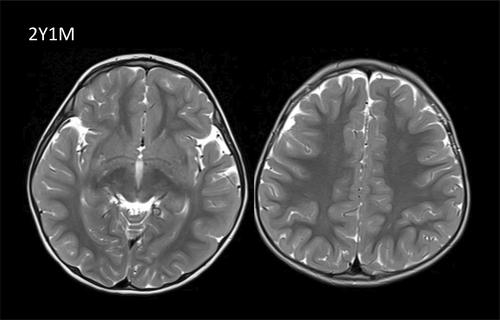

S- 腺苷同型半胱氨酸水解酶缺乏症是一种常染色体隐性遗传的先天性代谢错误,通过破坏蛋氨酸循环影响甲基化。其临床表现包括严重的围产期脑肌病和肝功能衰竭,以及孤立性高甲硫氨酸血症患者的无症状病程。我们报告了两例新的 S-腺苷同型半胱氨酸水解酶缺乏症病例,他们来自巴基斯坦,发病时无临床症状。两兄妹均表现为轻度慢性肝功能衰竭和肌酸激酶升高。年长的患者在 6 岁时出现孤立的语言处理障碍和轻度弥漫性白质营养不良,在限制蛋氨酸饮食 12 个月后可逆转。该患者在 7 岁时的肌肉核磁共振成像中出现了细微萎缩。S- 腺苷同型半胱氨酸水解酶缺乏症被确诊为 AHCY 基因中的同型错义变异 c.146G>A (p.Arg49His),这一基因型以前曾在巴基斯坦的轻症患者中报道过。饮食中蛋氨酸的限制降低了血浆蛋氨酸的含量,但没有降低血浆 S-腺苷高半胱氨酸和 S-腺苷蛋氨酸的含量。这项研究扩大了儿童无明显临床症状的 S-腺苷高半胱氨酸水解酶缺乏症的轻度范围,突出了南亚的一种特殊热点变异。这种轻度疾病很可能诊断不足,并提出了治疗管理的问题,以防止文献中记载的长期并发症,如肝细胞癌和成年早期肌病。

S-adenosylhomocysteine hydrolase deficiency is an autosomal recessive inborn error of metabolism affecting methylation by disrupting the methionine cycle. Its clinical spectrum spans from severe perinatal encephalomyopathy and liver failure to asymptomatic course in patients with isolated hypermethioninemia. We present two new cases of S-adenosylhomocysteine hydrolase deficiency from Pakistani origin clinically asymptomatic at presentation. Both siblings showed mild chronic liver failure and elevation of creatine kinase. The older patient presented at 6 years of age with isolated verbal processing difficulty and mild diffuse leukodystrophy, reversible 12 months after introduction of methionine dietary restriction. The patient showed subtle atrophy in the muscle MRI at the age of 7 years. S-adenosylhomocysteine hydrolase deficiency was confirmed with homozygous missense variant c.146G>A (p.Arg49His) in the AHCY gene, a genotype previously reported in Pakistani patients with mild presentation. Dietary methionine restriction decreased plasma methionine but not plasma S-adenosylhomocysteine and S-adenosylmethionine. This work expands the mild spectrum of S-adenosylhomocysteine hydrolase deficiency with no noticeable clinical symptoms in children, highlighting a specific hotspot variant from South Asia. This mild form of the disease is likely underdiagnosed and raises the question of therapeutic management to prevent long-term complications documented in the literature, such as hepatocellular carcinoma and myopathy in early adulthood.